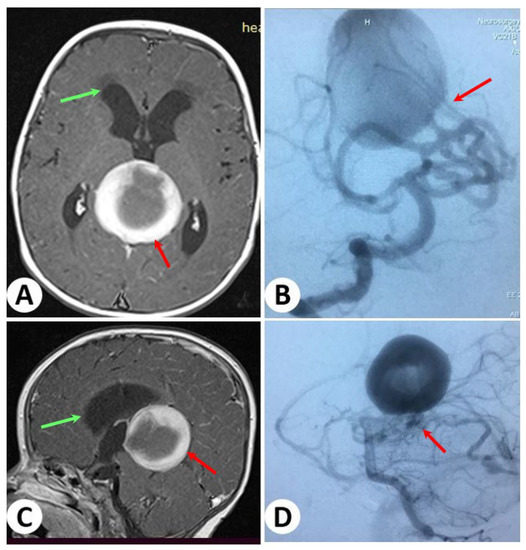

3.2. Illustrative Cases: Case 2